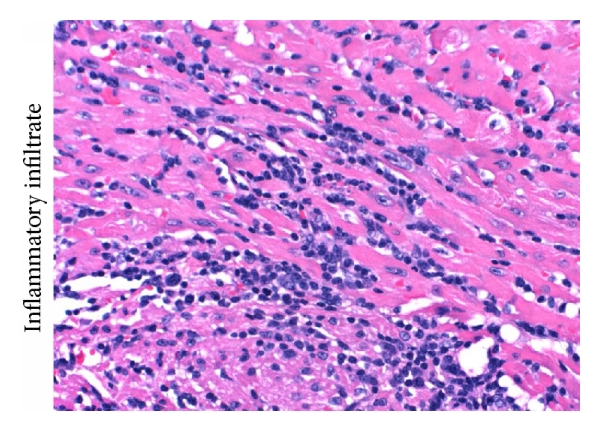

Analysis of the histological samples of heart muscle tissue collected after 16 days after inoculation revealed that WT mice presented more intact parasite nests and more amastigote forms within those nests (Figure 2(a)) than did 5-LO−/− mice (Figure 2(b)). In addition, there were greater inflammatory mononuclear cell infiltrates in WT mice (Figure 2(c)) than in 5-LO−/− mice (Figure 2(d)).

(a)

(b)

(c)

(d)